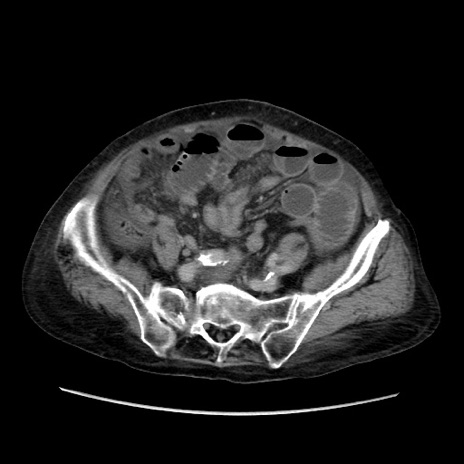

症例31(横断像)

【症例】80歳代 女性

【主訴】腹部膨満感

【現病歴】他院にて肝硬変にてフォロー中。1週間前から便秘、腹部膨満感、臍部腫瘤あり受診となる。

【既往歴】肝硬変

【身体所見】腹部膨隆あり、皮膚変化なし、疼痛なし。

【データ】WBC 4600、CRP 0.25